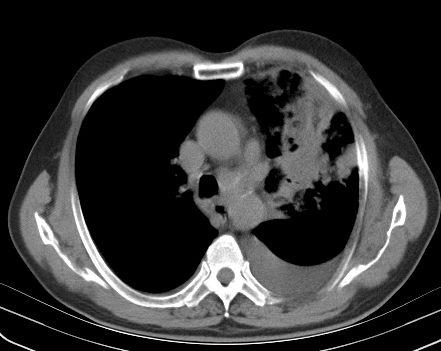

以下是引用老爱克斯新网客在2008-7-31 6:30:00的发言:[br]左肺上叶大片状病灶,左肺上叶支气管狭窄呈鼠尾状,左肺门增大,纵隔内见肿大淋巴结,左侧胸腔积液,余肺清晰。左肺中心型肺癌淋巴结转移,

以下是引用zjb在2008-7-31 6:32:00的发言:[br]左侧中心性肺癌 阻塞性肺炎 肺不张 胸腔积液 建议气管镜

以下是引用zjzjr在2008-7-31 8:45:00的发言:[br]考虑左侧中心性肺癌伴阻塞性肺炎,左肺上叶肺不张,纵隔淋巴结转移;左侧胸腔积液。建议行纤支镜检查。

以下是引用sdzyy在2008-7-31 8:47:00的发言:[br]病灶较治疗前有所进展,胸水增多, 左侧中心性肺癌 并 阻塞性肺炎 肺不张 胸腔积液 可能性大; 建议气管镜检查。 [br] [br]